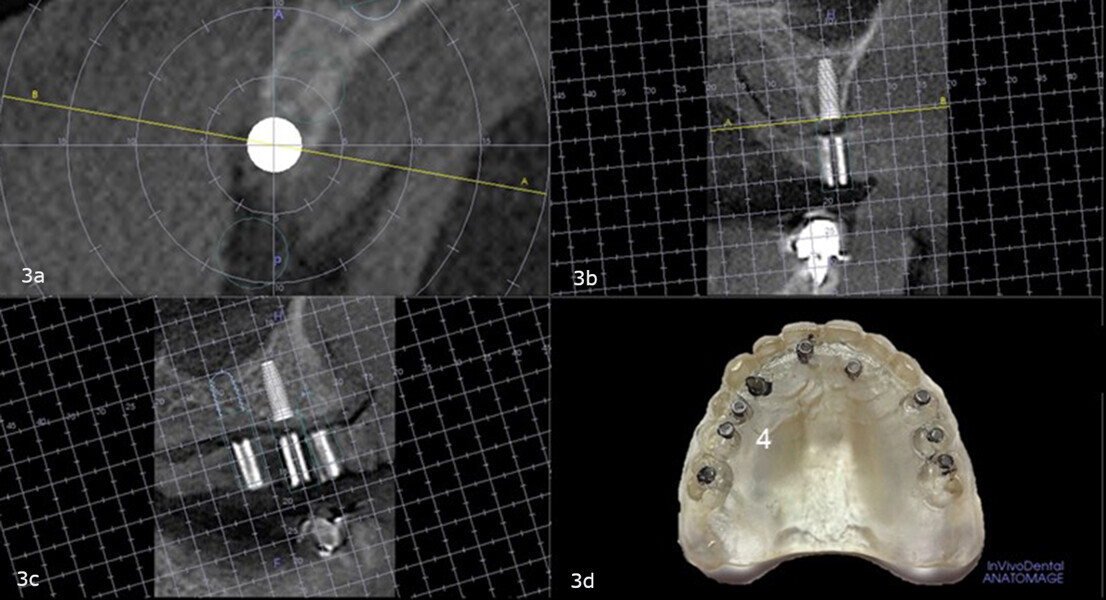

The maxillary right second premolar site was analysed, and it was determined that sufficient crestal height and adequate buccopalatal width were present to allow for implant placement (Figs. 3a-d). No correction would be required in the buccopalatal or mesiodistal directions. A 4.8 × 9.0 mm Astra Tech EV implant (Dentsply Sirona) was selected for this site.